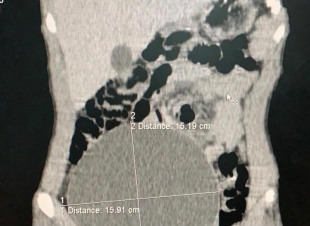

فريق طبي بمستشفى عفيف ينهي معاناة مريض من تورم في الجانب الأيمن للبطن